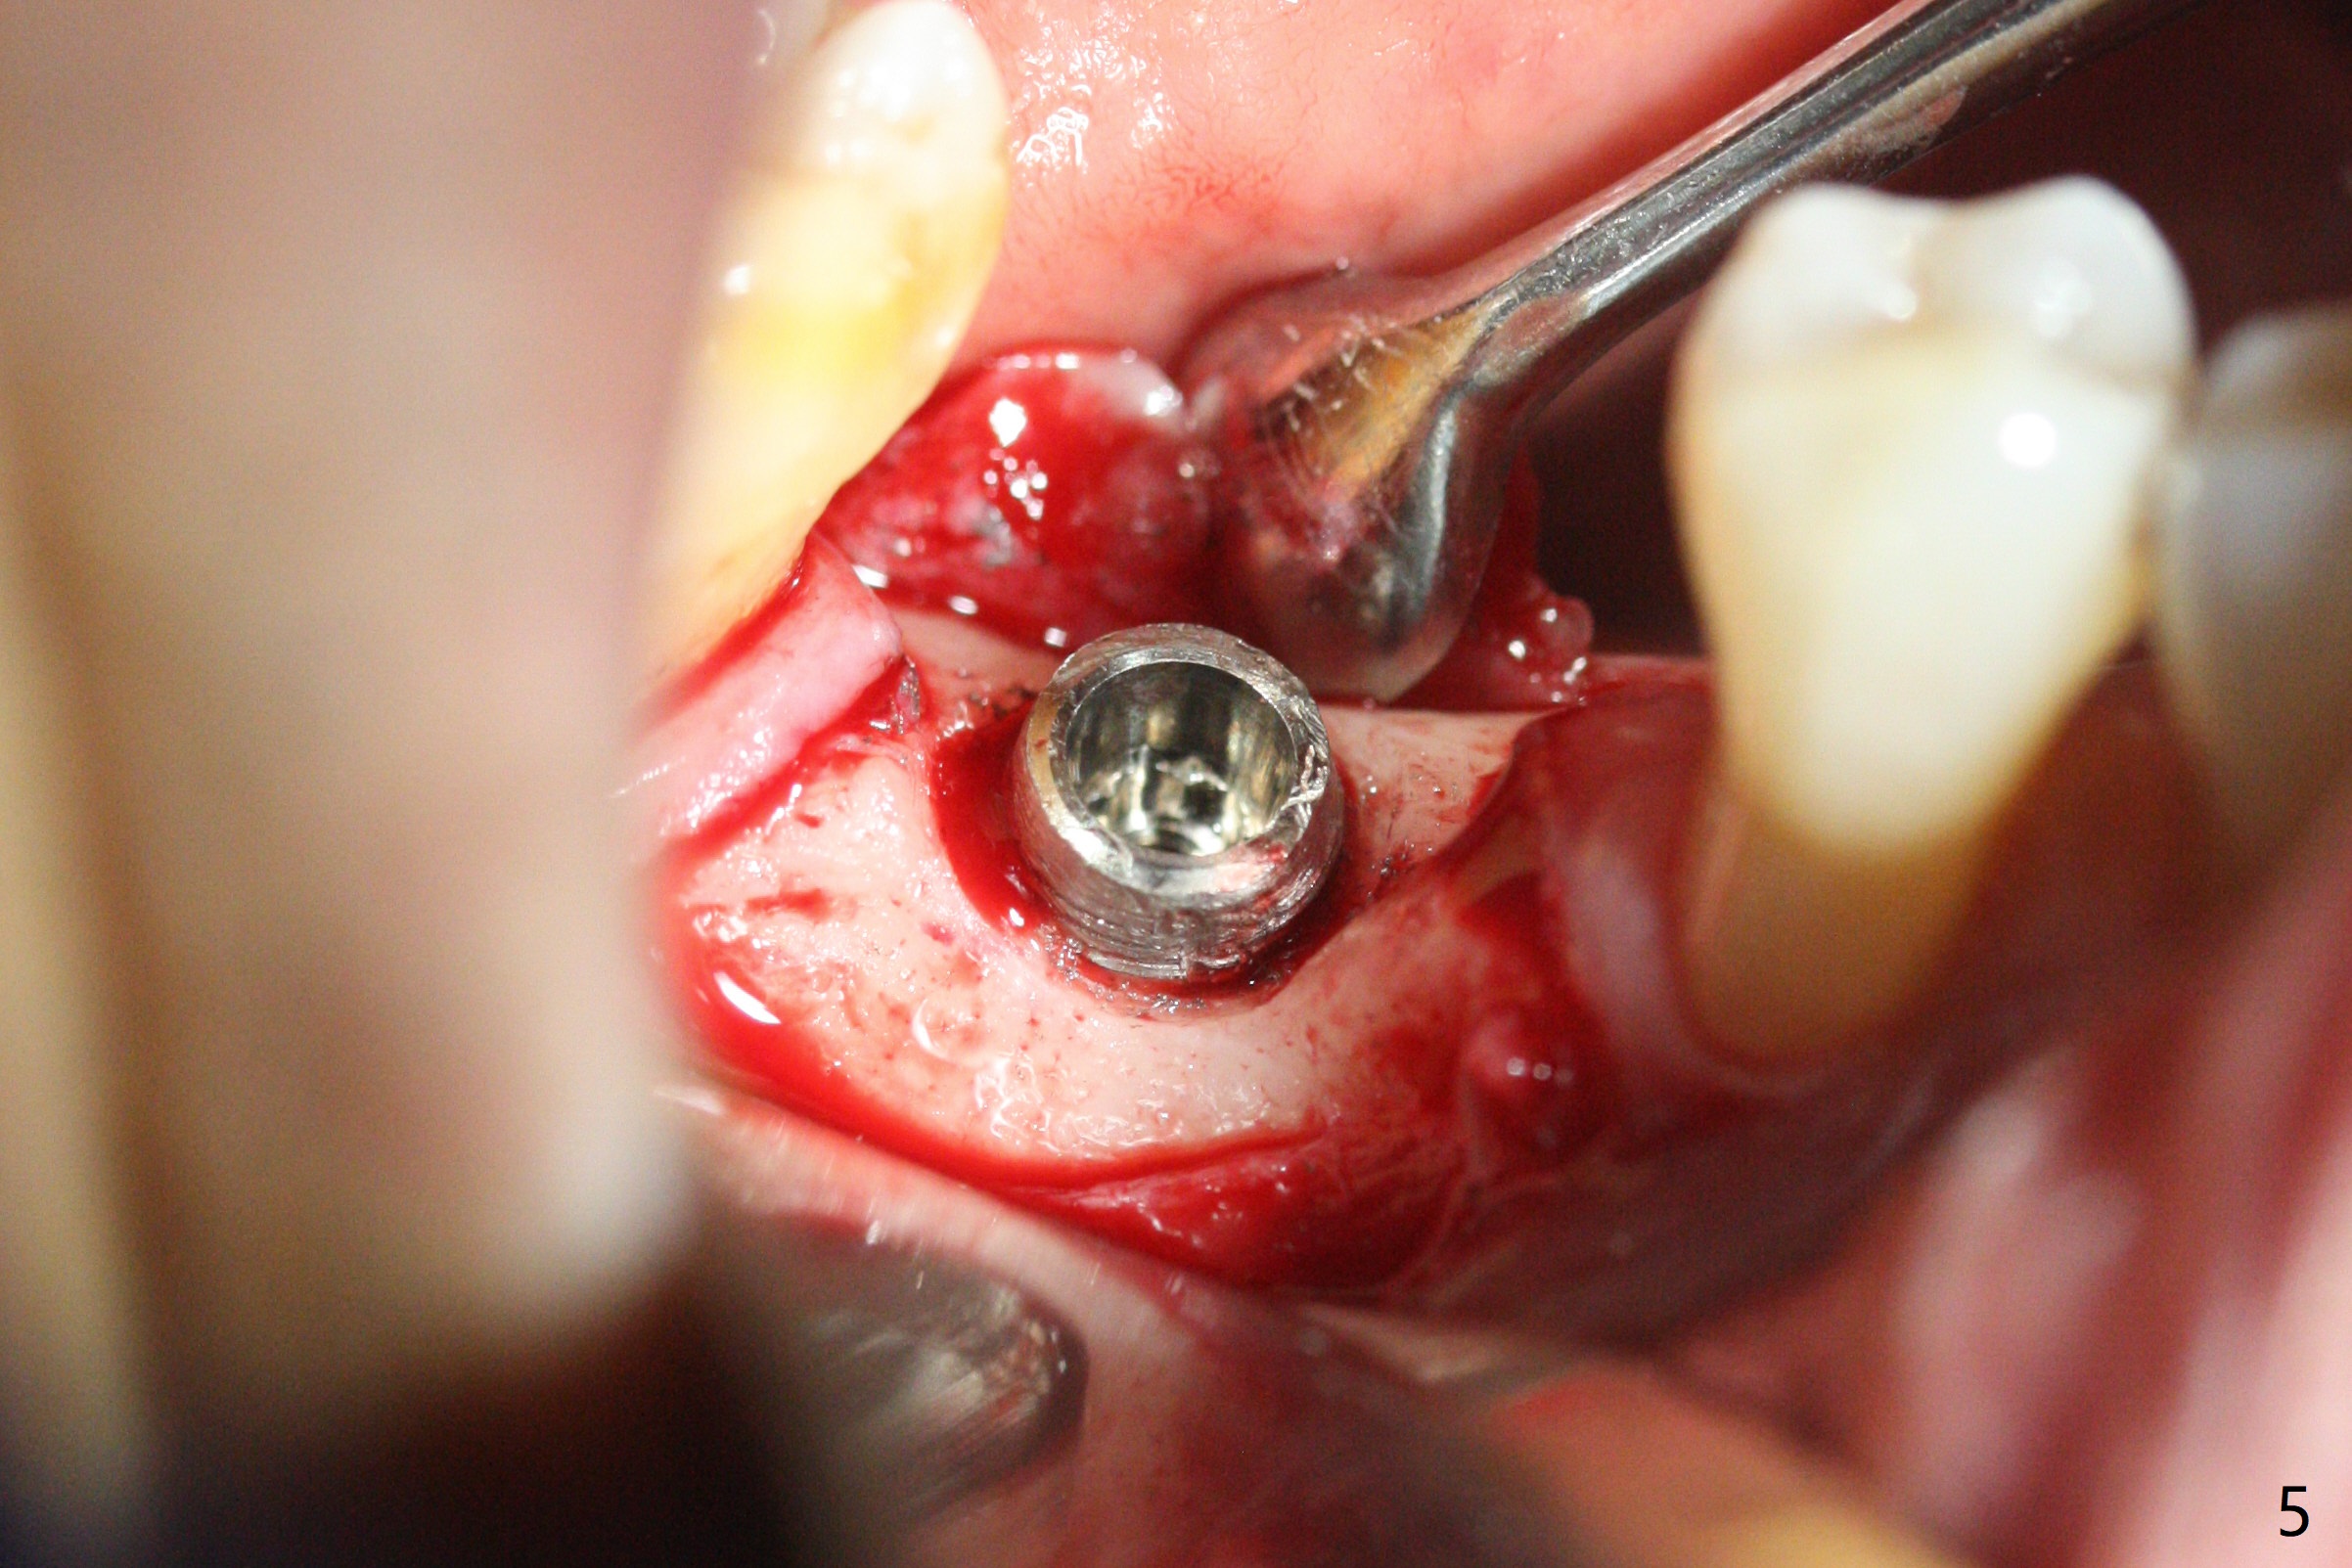

A 64-year-old man returns with history of a lump in the right submandibular region. Biopsy in a medical clinic shows inflammation. The implant crown at #30 has been cemented for ~ 4 years (Fig.1 (A: abutment)). The lingual plateau of the implant is exposed for 1-2 years asymptomatic (Fig.2 *). There is no deep lingual pocket when the crown and abutment are removed (Fig.3). Flap surgery confirms microthread exposure (circumferential, Fig.4). After removal of the microthreads with diamond bur (Fig.5), allograft (Fig.6 *), 6-month collagen membrane and a 6.5x5(3) mm healing abutment are placed. Following suturing, periodontal dressing is applied. The site remains asymptomatic 3 months postop, when an implant is placed subcrestal at #3.